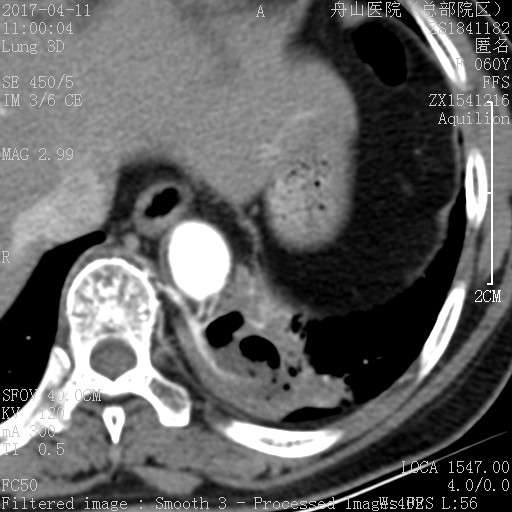

许多小白球--隐球菌,不做PAS及六铵银特染也看得清 荚膜的感觉明显 第三例的CT